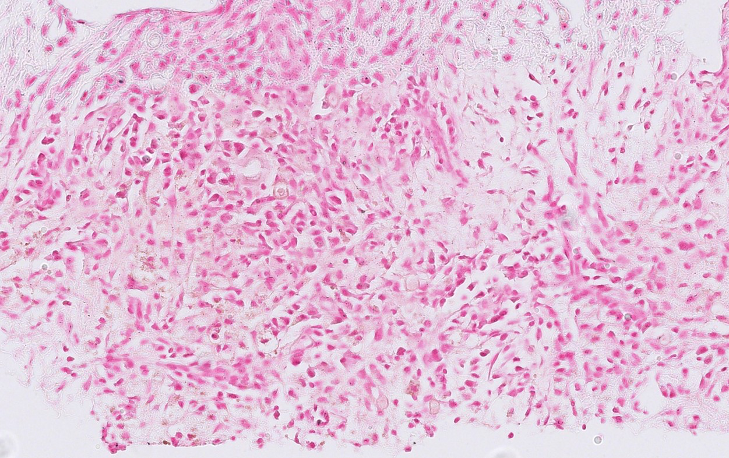

Figure 3. HE

• Fibroadipose tissue with a dense chronic inflammatory infiltrate composed predominantly of lymphocytes, plasma cells and numerous histiocytes, with scattered neutrophils.

• CD68 highlighted numerous histiocytes within the inflammatory infiltrate.